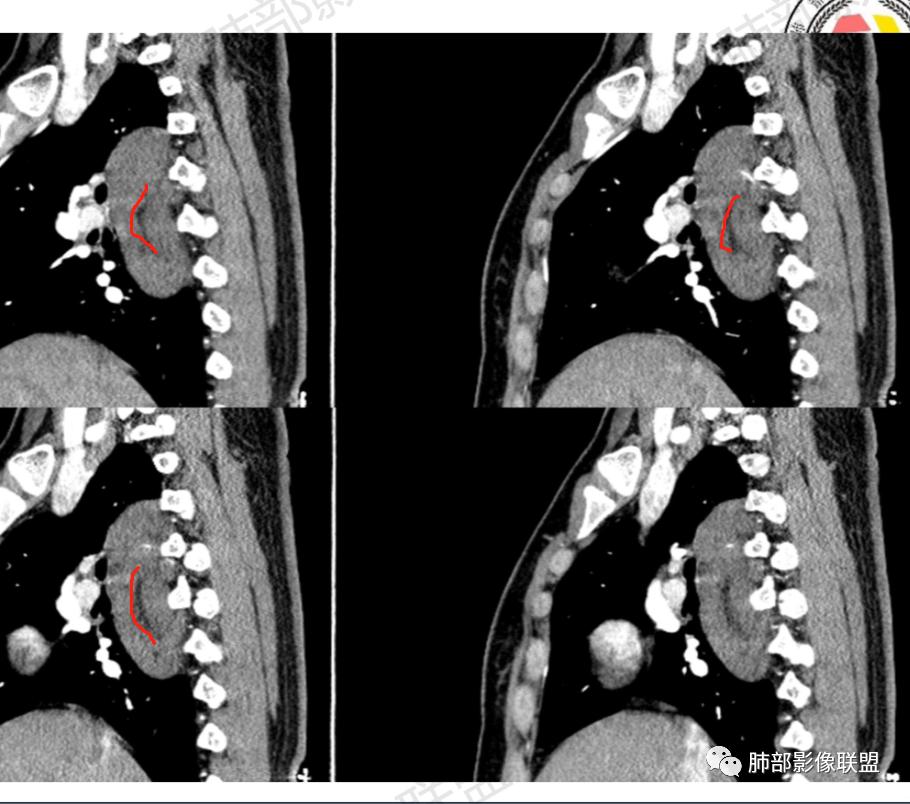

2.右后纵隔脊柱旁上下方向贴伏块影,“肾”形外观,边界清晰,密度不均,中央区域见脂肪密度影引向椎体前方,未见液性密度管腔影及钙化。

3.块影血供动脉来自肋间动脉,且由内后方侧入,其与下腔静脉之间未见回流通道。血管未见破坏,相邻组织未见侵入。

4.块影未延伸至椎管内,未见椎间孔扩大或骨质吸收破坏。

5.轻度渐进性强化。

1.肿块未横向经椎间孔延入椎管,或形成所谓“哑铃状”外观等,没有显示出沿脊神经根生长特征。长轴顺脊柱贴行恰好与交感神经路径相一致。

2.肿块含脂肪等成分,与交感神经路径相一致,渐进性轻度强化(可能含有粘液成分)等,以节细胞神经瘤最可能!尽管未显示“习惯性”的钙化。

瘤体体积常较大,大部分有完整包膜,边界清楚,可沿周围组织间隙嵌入性生长,由于肿瘤质地较软,使得肿瘤可呈多种形态,其易沿着周围组织间隙生长、包饶,但不挤压周围器官或组织,邻近血管被包绕或穿行,呈嵌入式或铸型生长方式,这是后纵隔神经节细胞瘤的特征性表现;

还有另外一种形态学特征,瘤体的上下径线常大于其他径线,这可能是神经节细胞瘤起源于交感神经节,而交感神经节纵向分布于近脊柱中线两旁及前方,导致了后纵隔神经节细胞瘤纵向生长的范围大于向其他方向生长的范围,其上下可跨越多个椎体。但后纵隔神经节细胞瘤体积较小时,则常呈圆形、椭圆形、哑铃形等形态,紧贴后纵隔或后胸壁。